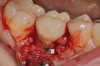

Fig 14. Clear resin cement left on the implant abutment.

Figure 14

Fig 15. Implant abutment following cement removal.

Figure 15